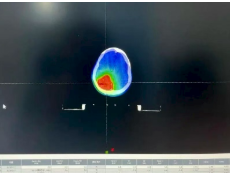

VitalBeam直线加速器落户达州市第三人民医院啦!现已正式投入使用。这个机器可大有来头,它就是在放疗界被誉为“放疗超人”的美国高端进口直线加速器,全市仅此一台。 三院肿瘤科开展放疗工作已有7年,年均放疗约6800人次,科室配套设施设备完善,放疗团队专业可靠,放疗技术成熟。VitalBeam直线加速器的引入使用,将填补我市精准放疗领域的空白,为三院放疗技术达到先进水平提供坚实保障,更为广大肿瘤患者带来新希望。 什么是放疗? 通俗来讲,放疗就是利用直线加速器产生的高能X射线,聚焦照射到肿瘤所在部位,从而杀灭肿瘤细胞。 据世界卫生组织(WHO)统计,目前约70%的恶性肿瘤病人需要在不同时期接受放疗。肿瘤患者中有45%是可以治愈的,其中放疗占18%,手术治疗占22%,化疗等其他治疗方式占5%。 VitalBeam直线加速器的四大优势  1、更快速 剂量率较以往的600MU/min大幅提升,最大可达到1400MU/min,对应的治疗时间从以往的15分钟以上缩短至平均3分钟左右。同时,治疗系统还通过“智能”自动化操作,进一步加快了治疗速度,缩短了治疗时间。这不仅让一些之前无法进行治疗的患者有了治疗机会,还能减少因治疗时间过长而带来的系统性误差和风险。  2、更安全 一方面来自于它的准确性,另一方面它在治疗区域之外的剂量跌落非常快,从而能有效地保护正常的组织和器官,此外,它还具备智能化的自动提示功能,可避免一些不必要的操作。  3、更精准 精度为0.5mm,相比于以往的1mm,精度提高了一倍。其次,它有一整套影像系统,能进行图像引导下(IGRT)的精准治疗,即使肿瘤在治疗期间因患者的呼吸而不断移动,系统依然可以准确捕捉肿瘤的位置。  4、更多功能 功能全面,可开展体部立体定向放射治疗(SBRT)、放射外科治疗(SRS)、图像引导放射治疗(IGRT)、呼吸门控治疗等多种先进治疗技术。 实际案例 使用VitalBeam直线加速器对一例脑胶质瘤患者放疗的步骤 放疗靶区勾画 采用MR和CT图像融合的方式,可准确区分病灶边界。 放疗计划设计 使用非共面旋转容积调强先进技术(VMAT)。 计划评估 处方剂量完全覆盖靶区(红色区域),靶区外正常组织剂量迅速跌落(正常组织受量更低)。 放疗实施 放疗时使用加速器自带锥形束CT进行图像引导(IGRT),自动对准靶区中心,实现了放疗可视化,放疗更加精准。   严格质控,保障质量 三院配备了先进的质控设备:晨检仪、二位矩阵和三维验证系统,定期进行加速器质检和放疗计划验证,确保加速器精度和放疗质量。 VitalBeam直线加速器主要适用于以下疾病 ●头颈部肿瘤:鼻咽癌、口腔癌、口咽癌、颈部肿瘤等; ●胸部肿瘤:肺癌、食管癌、乳腺癌、淋巴瘤及胸腺瘤等; ●腹部肿瘤:贲门癌、胃癌、肝癌、胰腺癌、结直肠癌等; ●泌尿生殖系统肿瘤:宫颈癌、卵巢癌、肾癌、生殖细胞肿瘤等; ● 四肢软组织肿瘤及各部位骨转移瘤; ●部分良性病变:垂体瘤、甲状腺眼凸等。 VitalBeam直线加速器的到来,无疑为三院肿瘤治疗注入了强大动力,我们将以更先进的技术、更专业的团队,为患者提供更优质的医疗服务,守护每一位患者的健康。